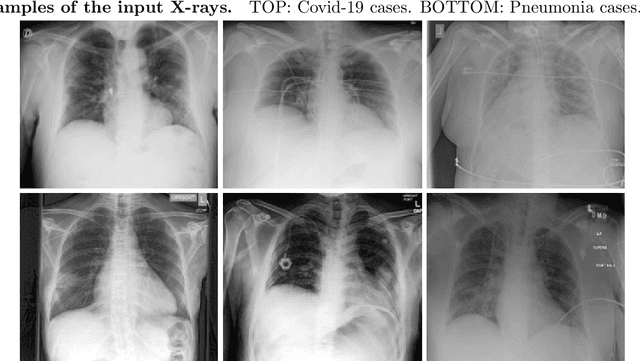

Abstract:Testing for COVID-19 has been unable to keep up with the demand. Further, the false negative rate is projected to be as high as 30% and test results can take some time to obtain. X-ray machines are widely available and provide images for diagnosis quickly. This paper explores how useful chest X-ray images can be in diagnosing COVID-19 disease. We have obtained 122 chest X-rays of COVID-19 and over 4,000 chest X-rays of viral and bacterial pneumonia. A pretrained deep convolutional neural network has been tuned on 102 COVID-19 cases and 102 other pneumonia cases in a 10-fold cross validation. The results were all 102 COVID-19 cases were correctly classified and there were 8 false positives resulting in an AUC of 0.997. On a test set of 20 unseen COVID-19 cases all were correctly classified and more than 95% of 4171 other pneumonia examples were correctly classified. This study has flaws, most critically a lack of information about where in the disease process the COVID-19 cases were and the small data set size. More COVID-19 case images will enable a better answer to the question of how useful chest X-rays can be for diagnosing COVID-19 (so please send them).